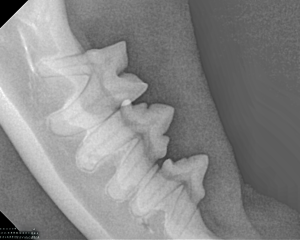

Canine Full Mouth Radiograph Example